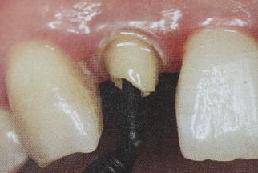

为防止裁剪过程中有可能造成桩表面的污染,可以粘结固位后再进行裁剪。

操作时,光固化灯应在树脂核成形后,颊、舌、合面分别光照20秒,在完成预备体后将其磨除。